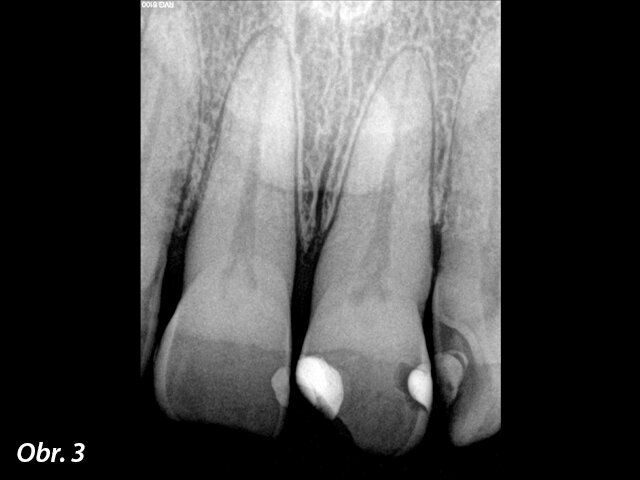

Výchozí RTG snímek.